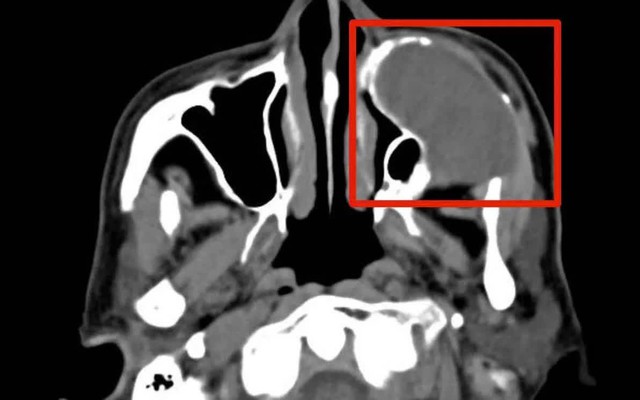

Kết quả chẩn đoán hình ảnh sau hội chẩn liên khoa ghi nhận khối u nhầy xoang hàm trái kích thước lớn, gây ăn mòn tiêu xương các thành xoang hàm và xâm lấn, phá hủy sàn ổ mắt. Các bác sĩ đánh giá, đây không còn là khối u lành tính đơn thuần; nếu tiếp tục trì hoãn, người bệnh có nguy cơ suy giảm thị lực không hồi phục, biến dạng vùng mặt và nhiễm trùng lan rộng.